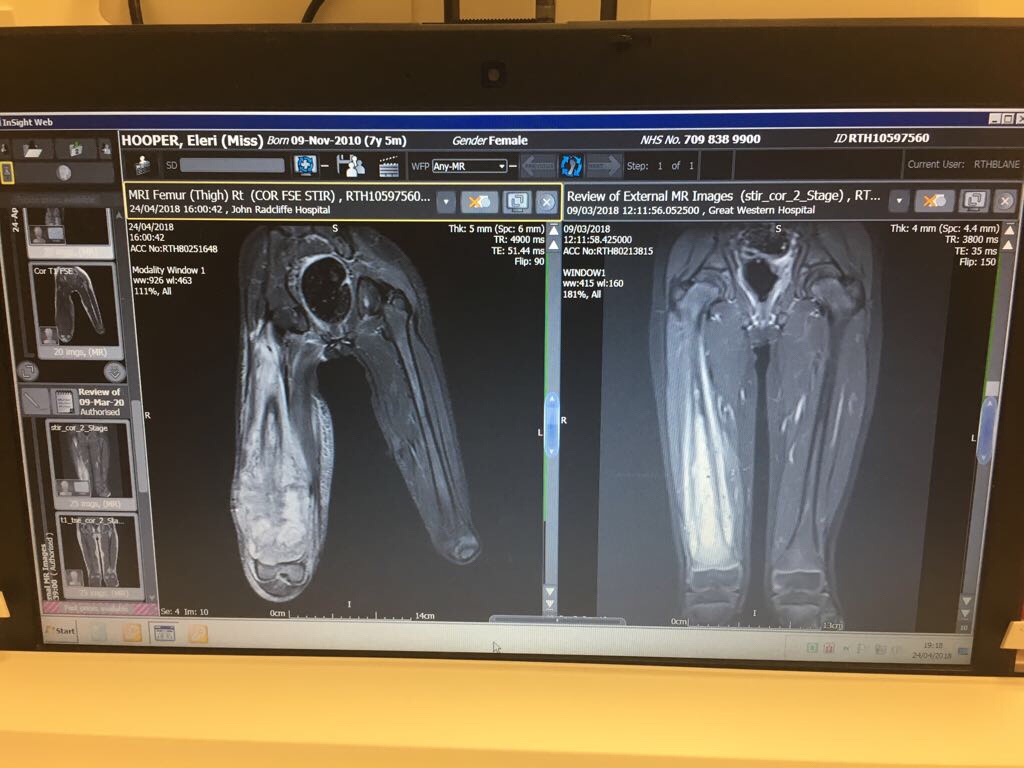

The last two weeks have see significant changes to Eleri’s treatment plan. After being admitted with a painful infection, it became obvious that the discomfort wasn’t necessarily completely confined to inflammation of tissue or necrosis associated with the death of cancer cells after chemotherapy. Her leg, or more specifically the tumour seemed to be getting bigger. On Tuesday 24 April they performed an MRI under general aesthetic. Our worst fears were confirmed – the tumour had continued to grow, it was almost at her hip and it hadn’t responded to the first two drugs of the chemotherapy protocol. Osteosarcoma is an aggressive form of cancer, but no one could have predicted the rapid acceleration in growth of Eleri’s tumour. We were told that she needed surgical intervention, but the oncologists were not sure what that intervention might be; it become clear that she might be heading for amputation. It took two days for a decision to be made on the exact surgery and treatment needed.